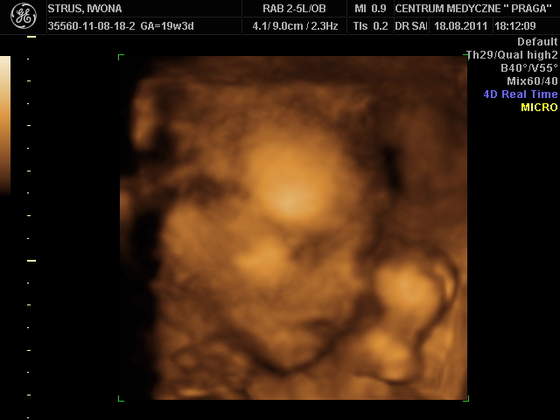

jej śliczny jest